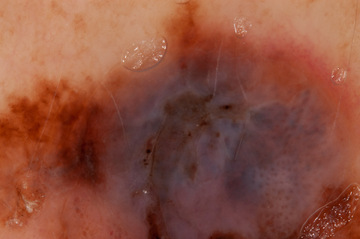

Case: 218